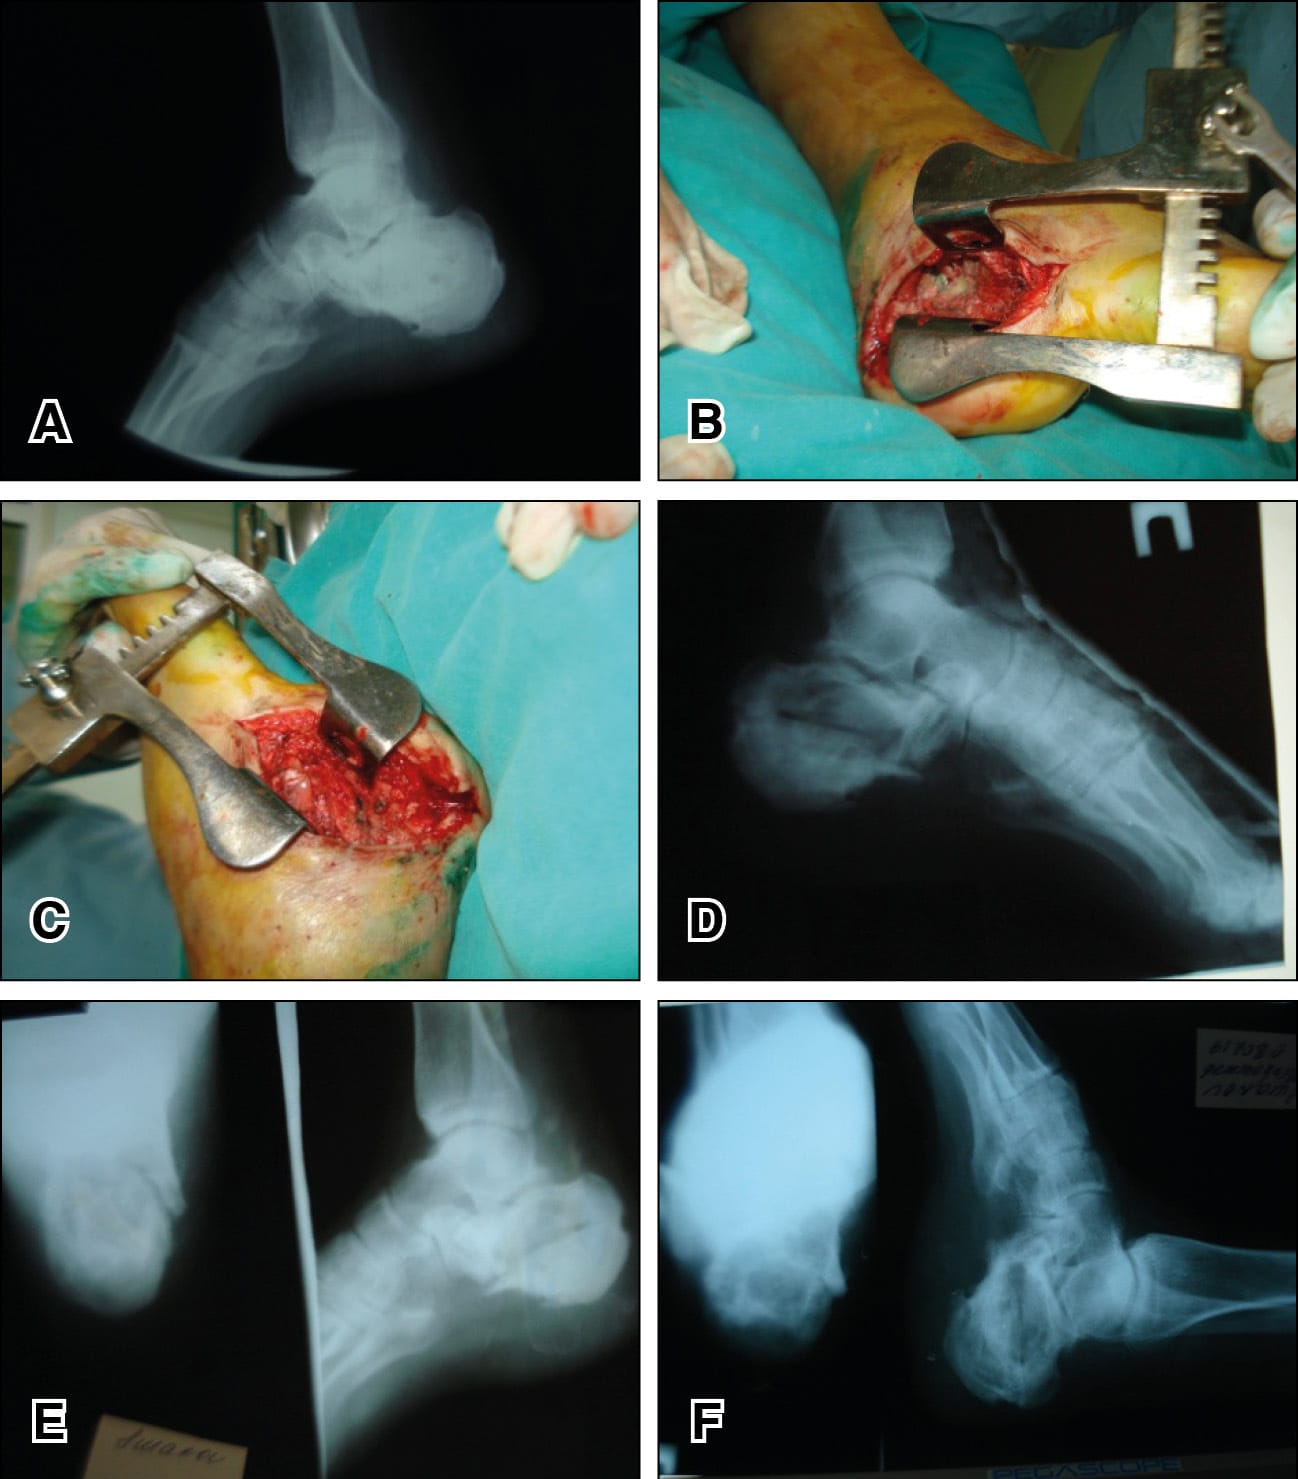

A 59-year-old male patient was admitted with pain in the right calcaneus. More than 2 years ago, he had an open fracture of the right calcaneus with wound healing problems and a fistula one month after surgery.

Diagnosis: chronic post-traumatic osteomyelitis of the right calcaneus.

Operation: Longitudinal osteotomy of the right calcaneus, intralesional resection to healthy tissues. Primary wound healing and after 2 months full weight bearing. x-rays at 6 months show a healed bony lesion and no complaints (Figure 1).